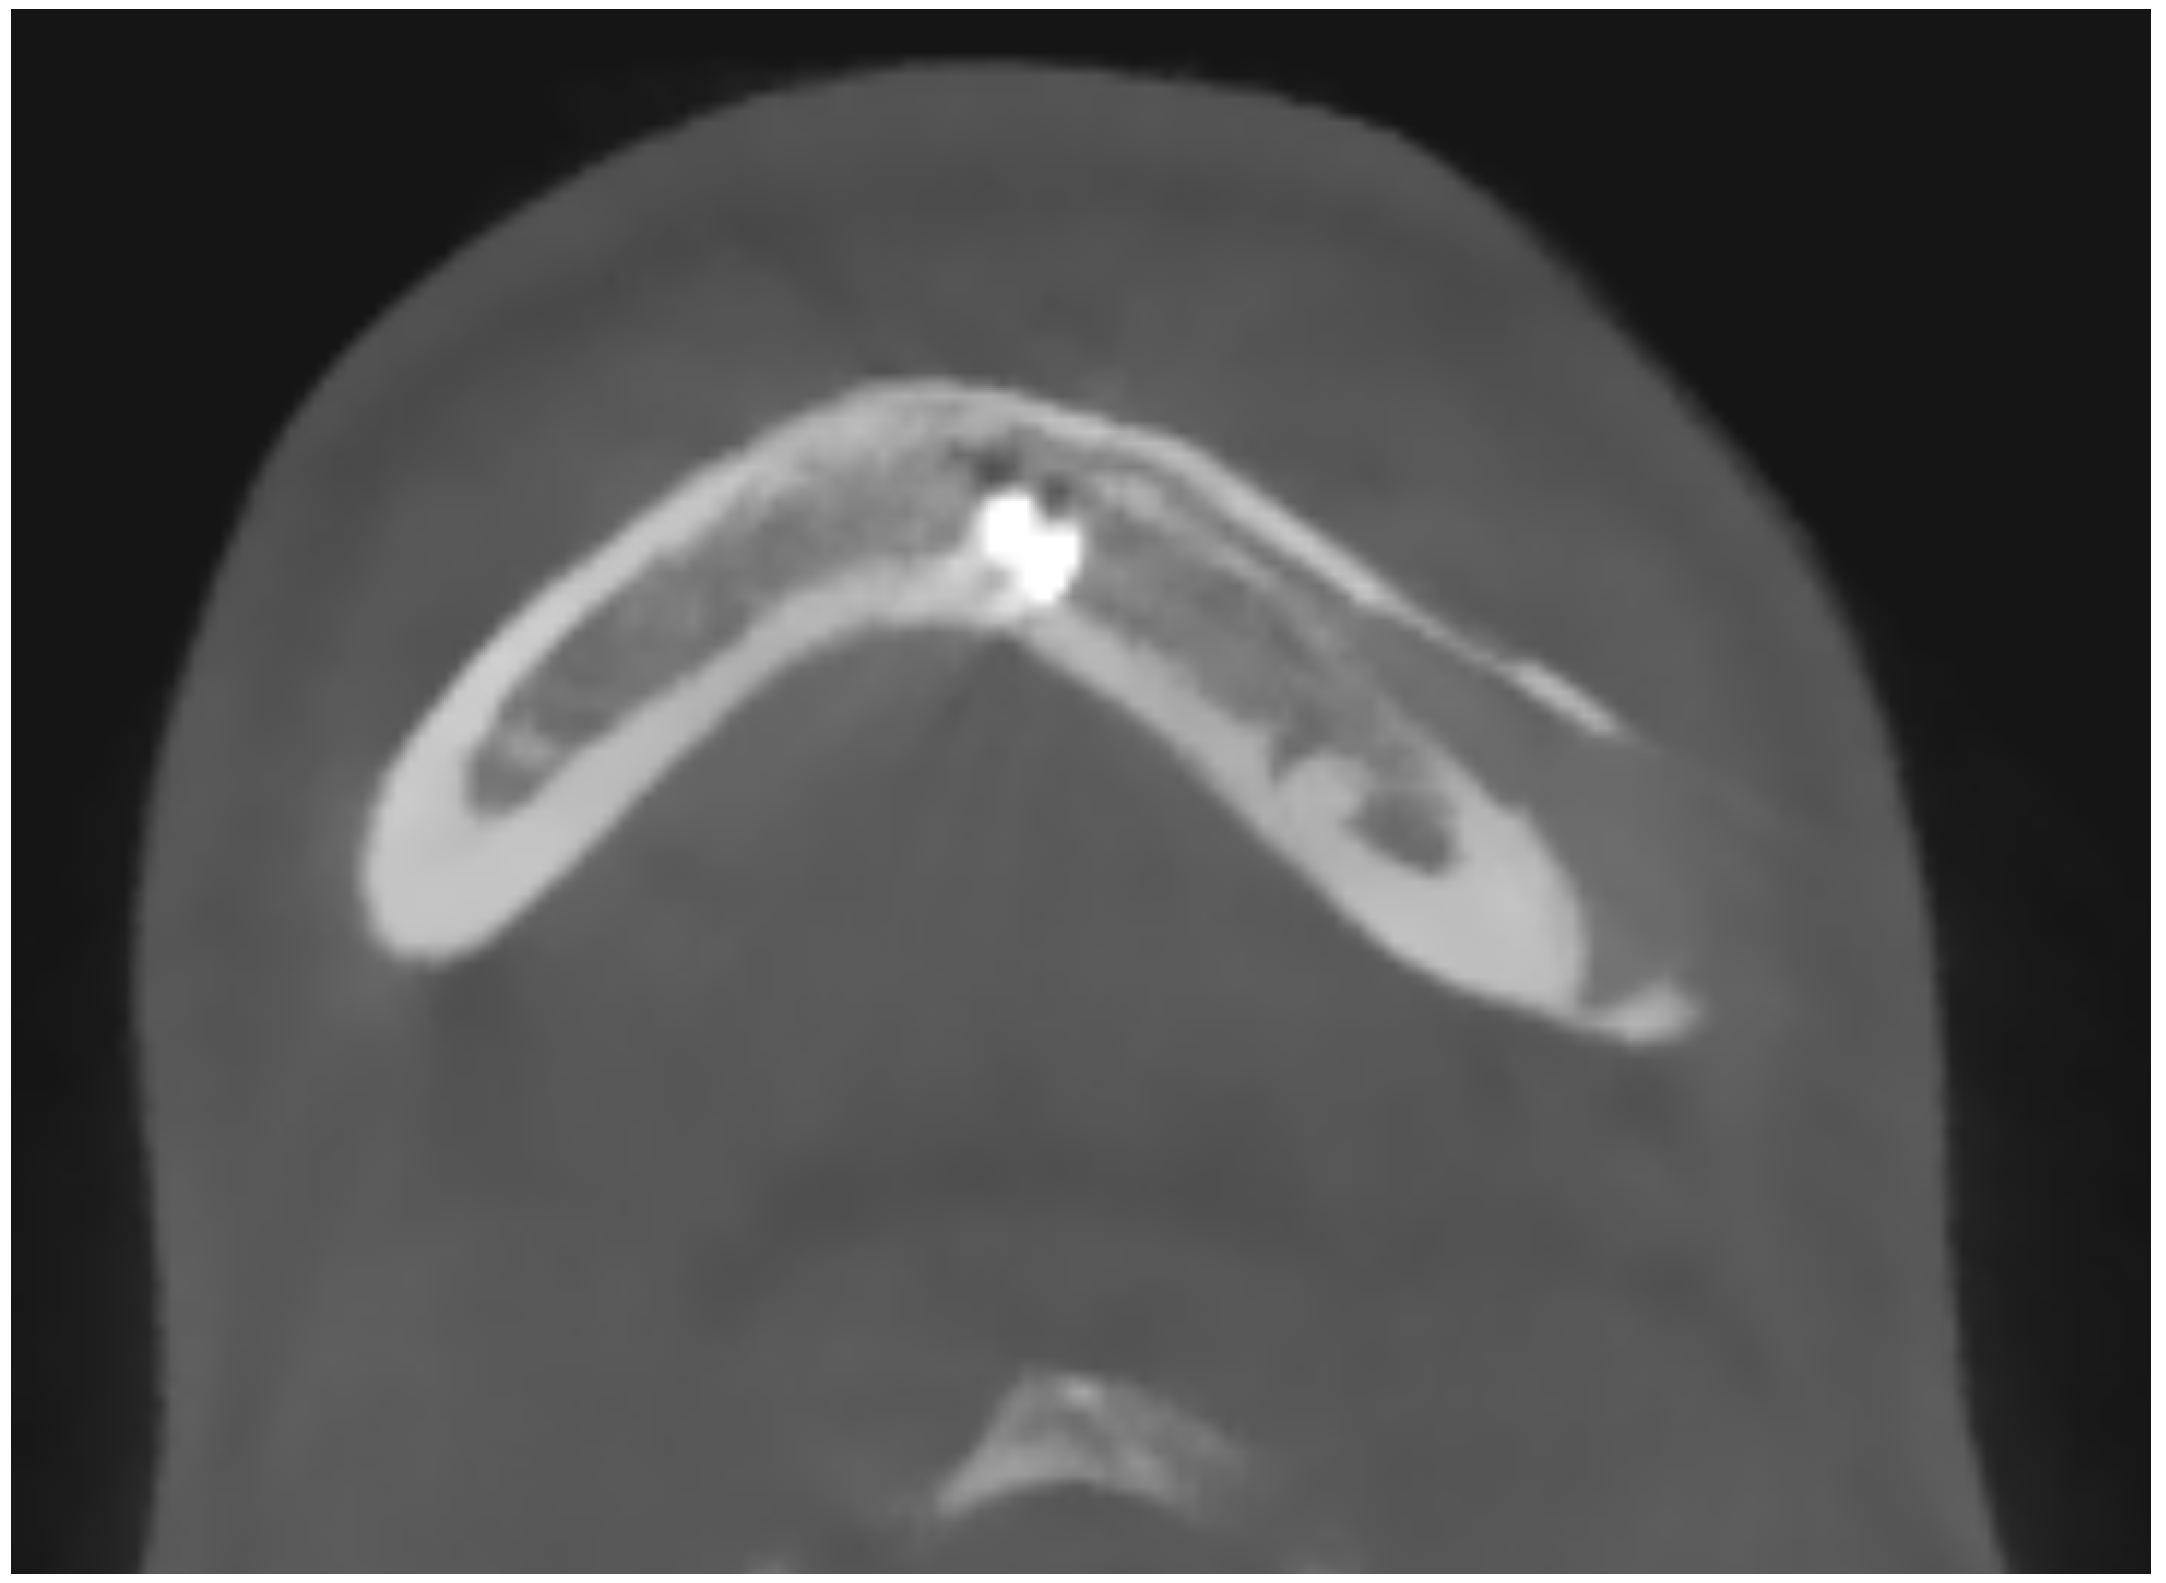

In 9 out of 10 CT scan radiological evidence of bone regrowth on the surface and edges of the implant was not evident. In one case, at 6 and 12 months, a bone regrowth consisting in islands of skull regeneration beneath the PEEK implant, at the interface bone-implant was documented. This was the case of a 34-year-old female patients with a history of head injury, who underwent autologous bone flap removal for infection along with wound dehiscence and secondary implant of PEEK defective cranioplasty. A retrospective analysis of the radiological exams revealed periosteal residual “spots” in the context of the defect, frontally. After PEEK cranioplasty, these spots expanded and fused to form a flake “regeneration front” of 25 mm length and 2.3 mm maximum thickness starting from PEEK-frontal bone interface [see Figure 1].

The case of neurosurgery underscores the potential of PEEK prosthetic implants to cause bone resorption in surrounding tissue (see Figure 2). In this instance, the observed bone resorption was minimal and did not require further intervention. Factors influencing this phenomenon include not only the material but also the design, mechanical loading, and notably, the interface between the implant and the periosteum. Titanium implants, while studies comparing different materials for craniofacial reconstruction are still limited, appear to be associated with increased donor site comorbidity, including bone resorption [35]. Countless studies have demonstrated that implants crafted from specific materials, such as titanium alloys, may induce peri-implant bone resorption attributable to stress shielding phenomena [36,37]. Stress shielding is a biomechanical phenomenon that leads to adaptive changes in bone strength due to the altered distribution of physiological loads on the bone, potentially leading to implant loosening. The elastic modulus of PEEK is comparable to those of cortical bone, so it exhibits less stress shielding than the Ti material [38]. Modifying PEEK through the addition of other materials, such as carbon fibers, is one of the techniques aimed at improving these effects, as observed in our case [39,40]. As mentioned previously, mechanical loading also plays a crucial role in potential bone resorption. Several studies have demonstrated that the mechanical behavior of implants under impact loading depends on the mechanical characterization of individual human tissues and regions [41]. This can influence the observation of bone resorption, as seen in our neurosurgical case. Finally, the micromotion of the implant, particularly observed in dental implants, could play a role in bone resorption, and help explain the case observed in neurosurgery. Therefore, careful consideration of these factors is crucial in mitigating bone resorption and ensuring the long-term stability of prosthetic implants.

Figure 2. The neurosurgery case representing bone resorption. (A): Lateral 3D view, loaded with low volume rendering; (b) Lateral 3D view, loaded with high volume rendering focusing on the PEEK prothesis and bone resorption underneath the prosthesis.